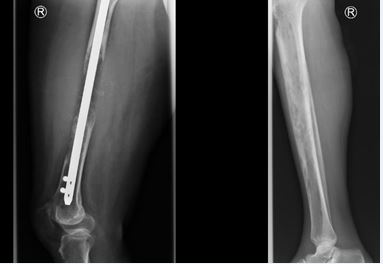

The onset of SRE’s has been shown to vary depending on the primary tumor, metastatic site and the radiological pattern. Tumors that form osteolytic metastatic lesions tend to cause more SREs such as pain and pathological fractures than those that form sclerotic lesions. In our study, half of the pathological fractures occurred in patients with osteolytic lesions and another 22.7% in

mixed lytic and blastic lesions. This emphasizes on the risk of pathological fractures in patients with osteolytic lesions (Figure 4).

https://www.jscimedcentral.com/public/assets/images/uploads/image-1768992541-1.JPG

Figure 4 Osteolytic lesions; X ray images in a lady who had impending fracture of the femur (Left) which was fixed by intramedullary nailing and then later presented with metastatic osteolytic lesion involving the shaft of the Tibia (Right).